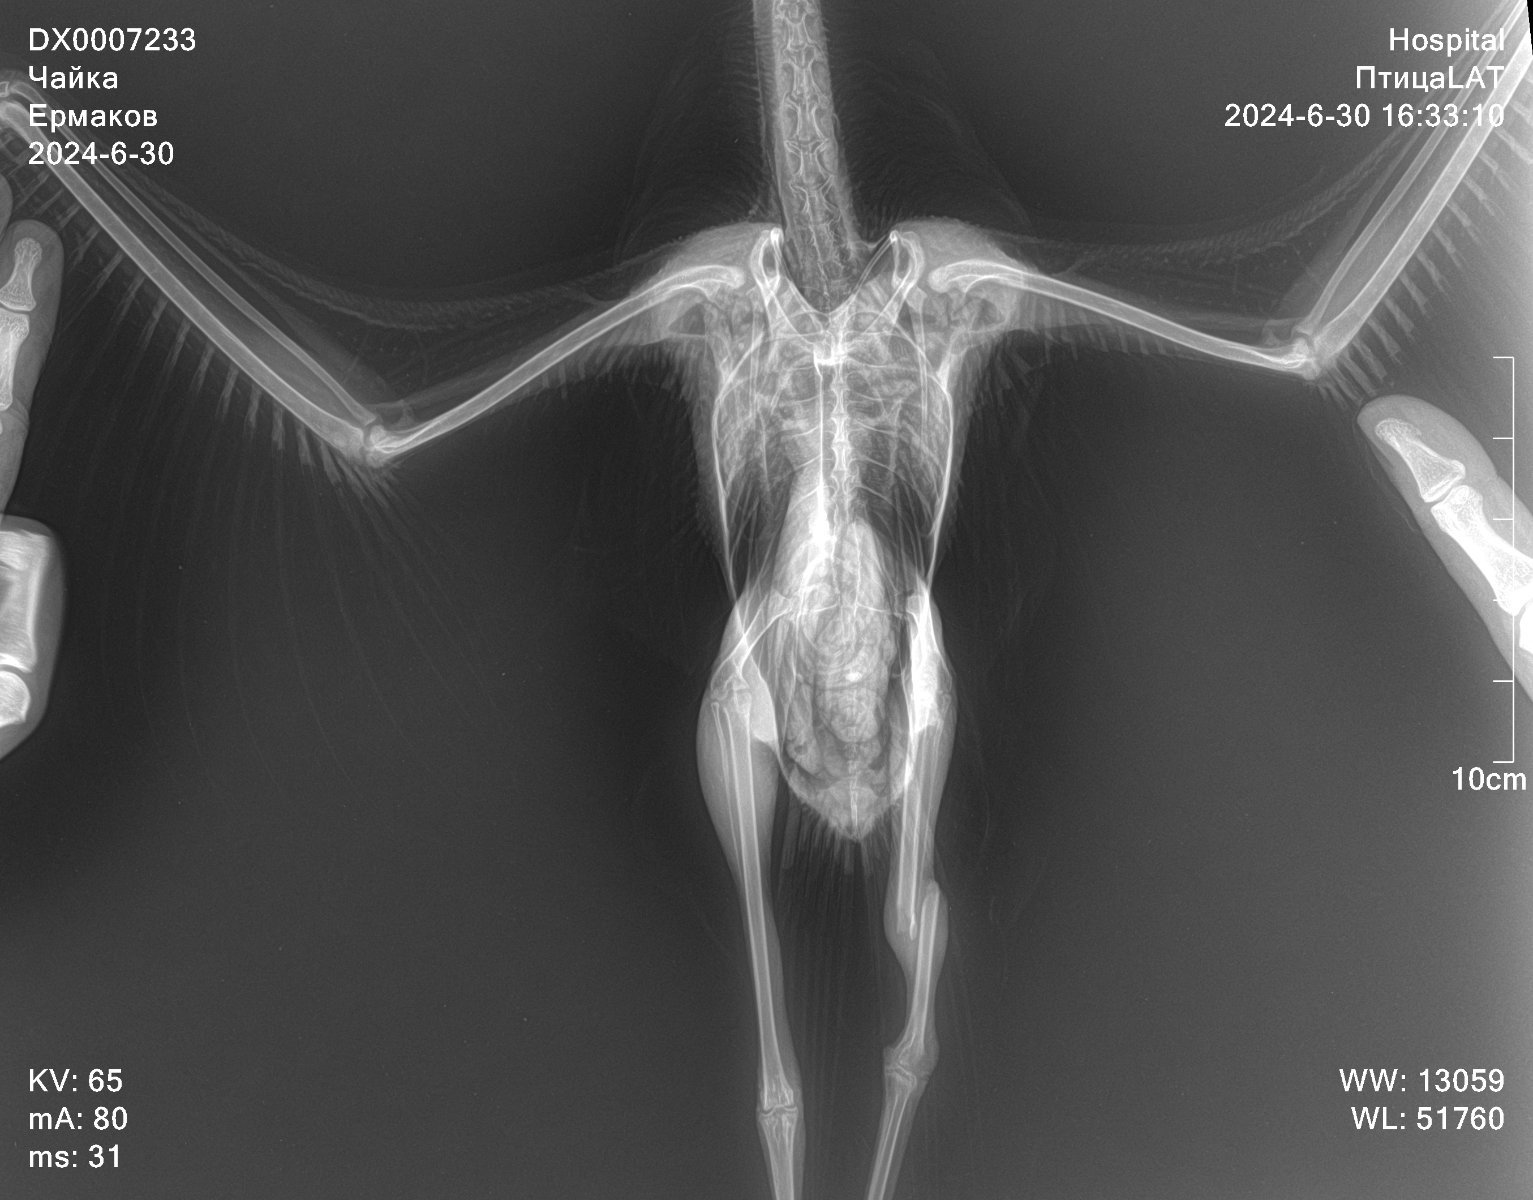

Добрый вечер. Подобрали птенца чайки со сломанной лапкой. Открытый перелом правой лапки. Чайку прооперировали. Поставили спицы. Лапка восстанавливается. Левая лапка была здоровая. Но при транспортировки к орнитологу, что-то случилось с лапкой. Держит в согнутом виде, не выпрямляет и не встает. Делали рентген. На нем нет вывихов и переломов левой лапки. Снимок рентгена перед операцией. повредили левую лапку 29.06.2024 операция правой лапки была 02.07.2024. Данный снимок был сделан 06.07.2024 16.07.2024 делали повторный рентген, чтобы проверить правую лапку после операции. Левую тоже смотрел неоднократно, но никто из врачей не может сказать что с левой лапкой. Подскажите пожалуйста, что может быть с левой лапкой, как восстановить? Для птенца сделаны качели, чтобы снизить нагрузку на лапы.